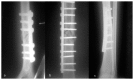

Fig. 3

a, b, c - Osteosynthesis. a) Left humerus; b) left femur; c) right tibia.